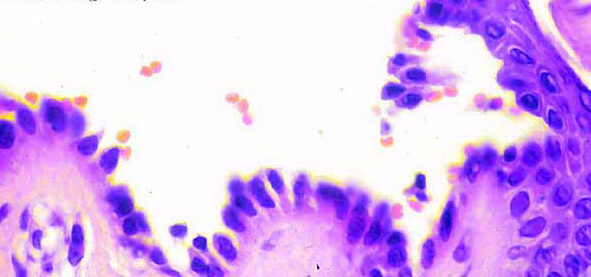

The earliest recognized change may be either eosinophilic spongiosis rarely or, more commonly, “spongiosis” in the lower epidermis . This spongiosis may actually represent the earliest manifestation of acantholysis rather than true spongiosis as defined earlier. Acantholysis leads first to the formation of clefts and then to blisters in a predominantly suprabasallocation . The intraepithelial acantholysis may extend into adnexal structures or occasionally be higher in the stratum spinosum. The basal keratinocytes, although separated from one another through the loss of attachment, remain firmly attached to the dermis like a “row of tombstones.” Within the blister cavity, the acantholytic keratinocytes, singularly or in clusters, have rounded condensed cytoplasm about an enlarged nucleus with peripherally palisaded chromatin and enlarged nucleoli. In some patients, there are varying quantities of antidesmoglein 1 and antidesmoglein 3 antibodies, leading to variable planes of acantholysis. There is little inflammation in the early phase of blister formation. If present, it is usually a sparse, lymphocytic perivascular infiltrate accompanied by dermal edema. However, if eosinophilic spongiosis is apparent, numerous eosinophils may infiltrate the dermis. The phenomenon of eosinophilic spongiosis occurs occasionally in other blistering diseases, particularly in their early phases, including acute contact dermatitis, pemphigus foliaceus, bullous pemphigoid, herpes gestation is, drug eruptions, spongiotic arthropod bite reactions, and transient acantholytic dermatosis. Several important changes ensue as the lesions age. First, a mixed inflammatory cell reaction consisting of neutrophils, lymphocytes, macrophages, and eosinophils may develop. Because of the instability of the blister roof, erosion and ulceration may occur. Older blisters may also have several layers of keratinocytes at the blister base because of keratinocyte migration and proliferation. Last, there may be considerable downward growth of epidermal strands, giving rise to so-called villi (Fig. 9-9D). The evaluation of patients with only oral lesions is difficult, because intact blisters are rarely encountered due to the trauma of mastication, and biopsies may show only erosion and ulceration. Indeed, it is best to sample the edge of a denuded area with intact mucosa in an attempt to demonstrate the typical pathologic changes. Clinicians frequently cannot distinguish between an ulcer and the intact mucosa, as both are often white and shaggy. In patients with only oral lesions, biopsies of intact oral mucosa for DIF testing are more sensitive than biopsies of lesions for routine light microscopic evaluation. Therefore, biopsy from the normal maxillary and upper buccal mucosa is necessary when there is extensive ulceration. Cytologic examination using a Tzanck preparation is useful for the rapid demonstration of acantholytic epidermal keratinocytes in the blisters of pemphigus vulgaris. For this

purpose, a smear is taken from the underside of the roof and from the base of an early, freshly opened bulla. Giemsa stain is applied with subsequent rinsing and air-drying.

Because acantholytic keratinocytes are occasionally seen in various nonacantholytic vesiculobullous or pustular diseases as a result of secondary acantholysis, cytologic examination represents merely a preliminary test and should not supplant histologic examination.